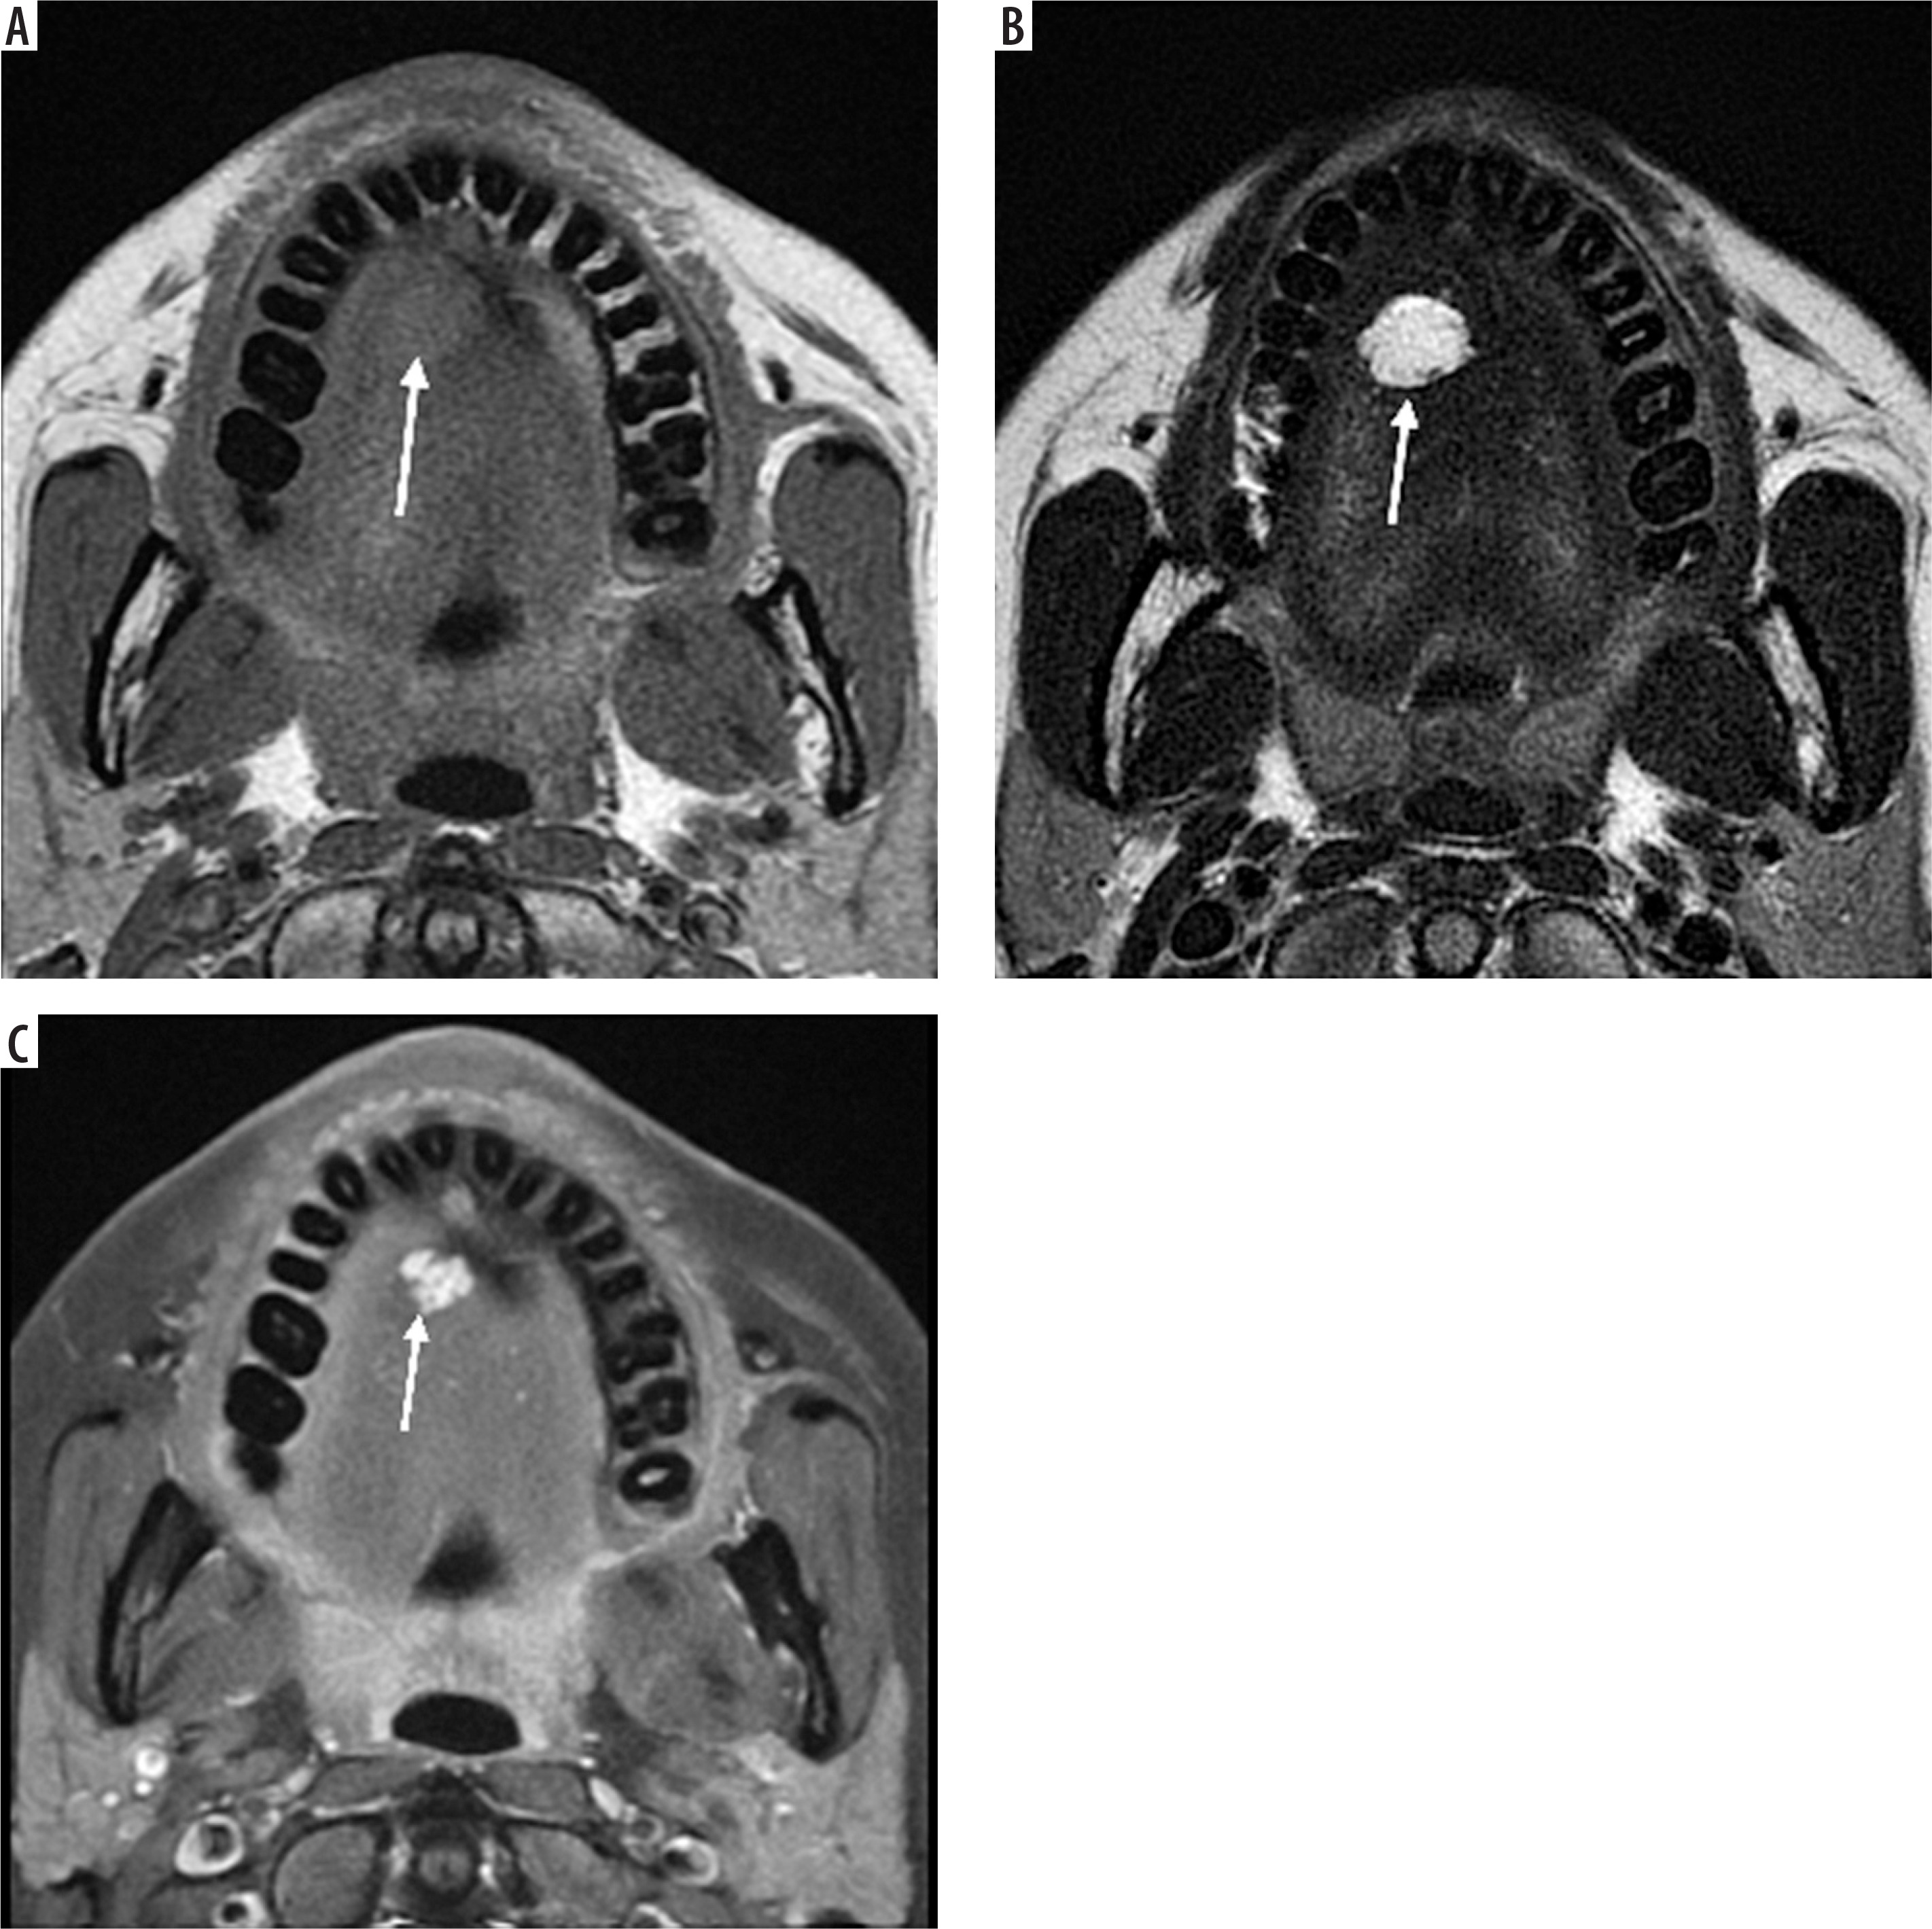

Case 4: Tongue haemangioma

A 25-year-old female presented with a bluish nodule on the ventral aspect of the tongue. On MRI, the lesion appears well defined and isointense to mildly hypointense compared to the surrounding muscle on the T1-weighted image (Figure 7A). It demonstrates a classic hyperintense appearance on the T2-weighted sequence, a hallmark feature of fluid rich or vascular lesions (Figure 7B). Post-contrast, T1-weighted, fat-saturated (T1 C+ Fat sat) imaging shows strong enhancement of the lesion, confirming its vascular nature (Figure 7C).

Figure 7

Axial section of MRI of tongue haemangioma: A) T1-weighted, B) T2-weighted, C) T1 C+ Fat sat. These findings are essential for distinguishing haemangioma from other tongue masses and for assessing lesion extent and vascularity, which is critical for safe surgical excision and functional preservation [Courtesy: Radiopaedia. DOI: https://doi.org/10.53347/rID-84386, rID: 84386]